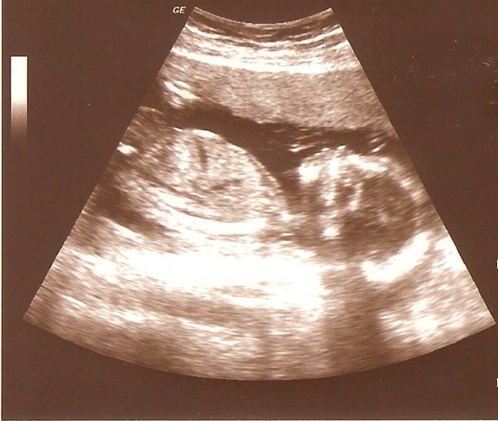

Fazit: Es ist alles in Ordnung - wie im Lehrbuch. Und das freut mich natürlich sehr. Gerade, weil ich immer solche Probleme mit dem Essen und der Psyche habe. Aber solche Bilder entschädigen ja für alles.

Das Geschlecht verschweige ich weiterhin, aber eine Pofilaufnahme möchte ich schon herzeigen - weil es ein zu schönes Bild ist. Ich hoffe, man kann es gut erkennen...

| 19 + 3 |